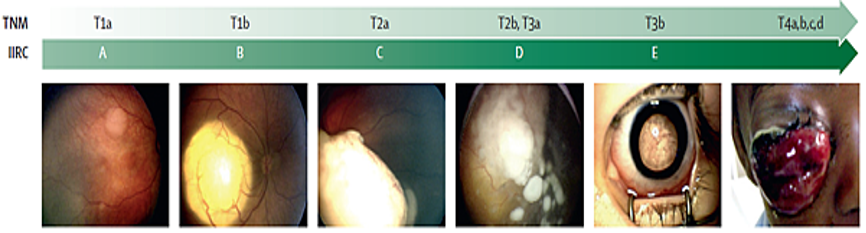

在1958年,Reese-Ellsworth(R-E)分期率先提出,當時是針對"放射線治療的預測效果"而提出的,之後有更多不同治療方法出來,原先分期方法逐漸不合需求。1960 年代視網膜母細胞瘤的治療以放射線治療為主,治療的成效取決於腫瘤的大小及位置,Reese and Ellsworth (R-E) 的分級可以作為預後的參考。1990年後化學治療結合局部治療取代了放射線治療,腫瘤細胞有無玻璃體( vitreous seeding)及視網膜下散播(subretinal seeding),成了影響預後的指標,ICRB classification systems 成了新的通用分級 ( 表1 )。

A、B級的腫瘤因體積小無玻璃體散播及網膜下散播範圍不大,在結合化學治療和局部冷凍或鐳射熱能治療後,通常成效佳腫瘤得以控制。反之,D、E級的腫瘤因體積大,又玻璃體散播及網膜下散播範圍廣,即使集合多項治療成效依然悲觀,E級的腫瘤則絕大部份需要眼球摘除手術。

資料來源: Lancet 2012; 379: 1436–46

分期屬於E分期的病人,已經有遠端轉移的風險,因此會建議腦脊髓液與骨髓穿刺檢查,確保有無腦膜或是骨髓腔註轉移,若是已經轉移表示屬於末期疾病,需要高劑量化療與異體骨髓移植。